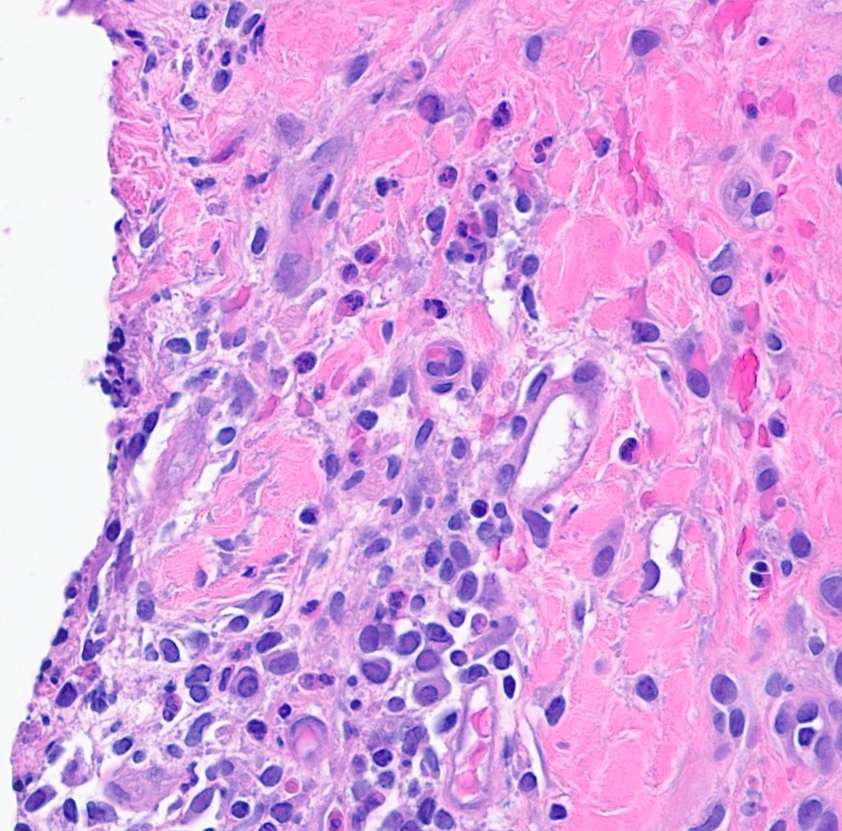

I'm so honored to receive the Dermatopathology Trainee World Cup 1st place for my presentation on cysts mimicking malignancies with Drs. Foulis and Gibbs! Had a great time, learned a lot, and met many amazing people @IntSocDermpath #ISDP2023 #PathTwitter #dermpath #dermtwitter